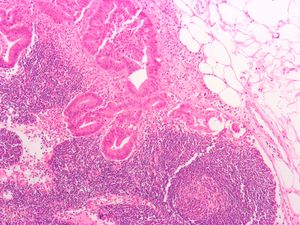

Micrograph of a tubular adenoma, a type of colonic polyp and a precursor of colorectal cancer.

Micrograph of an invasive adenocarcinoma (the most common type of colorectal cancer). The cancerous cells are seen in the center and at the bottom right of the image (blue). Near normal colon-lining cells are seen at the top right of the image.

Histopathologic image of colonic carcinoid stained by hematoxylin and eosin.